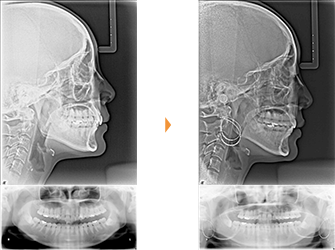

| 主訴 | 前歯の突出が気になる |

| 年齢・性別 | 28歳 / 男性 |

| 治療方針 | 上顎前突及び過蓋咬合。下顎の後退感が顕著なため、口元の突出感が目立つ。下顎前歯の1歯欠損と左側大臼歯に鋏状咬合がある。完全に突出感を改善するのは困難と思われるが、できる限り上顎前歯を後退させる。 ※治療後オトガイ部の緊張がとれて、プロファイルはある程度改善できた。 |

| 抜歯部位 | 上顎左右第1小臼歯、下顎前歯、左右第3大臼歯(親知らず) |

| 使用装置 | 歯科矯正用アンカースクリュー、マルチブラケット装置 |

| 治療期間 | 38か月 |

| リテーナー | 上顎インビジブル、下顎インビジブル |

| 費用 | 840,000円(税別) |